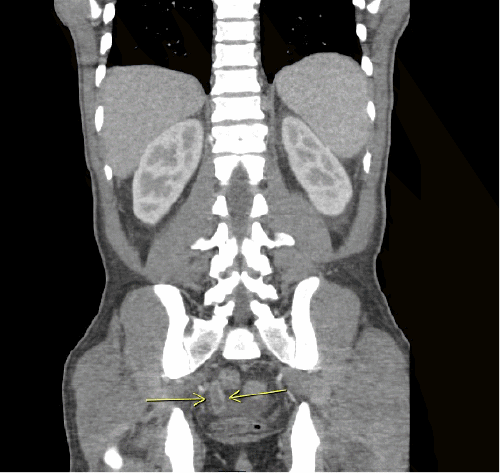

On physical examination, his vitals were within normal limits. He was very thin and had diffuse palpable lymphadenopathy in the cervical and inguinal regions and a large mobile left cheek mass. His abdominal exam was benign, with no anterior abdominal pain but rather bilateral flank pain. The patient's leukocytosis was 13,000 k/cm2, with the remainder of his labs within normal limits; the cluster of differentiation 4 (CD4) count was 2670, and the viral load was 1,391,823. HTLV-I/HTLV-II antibodies were positive. A CT of the abdomen and pelvis with oral and intravenous (IV) contrast was obtained, showing acute tip appendicitis (Figure 1) and extensive bulky gastrohepatic, periportal, peripancreatic, retroperitoneal/para-aortic, bilateral iliac chain, and bilateral inguinal lymphadenopathy (LAD) (Figure 2) with mild splenomegaly suggestive of lymphoma. A CT maxillofacial scan to evaluate his cheek mass also demonstrated extensive bulky cervical lymphadenopathy as well as an enlarged mandibular mass (Figure 3). Of note, the patient had a CT scan performed one year prior that showed an appendix with the same diameter but no local inflammation (Figure 4).

Figure 2. CT Scan: Abdominal and Inguinal Lymphadenopathy. Published with Permission